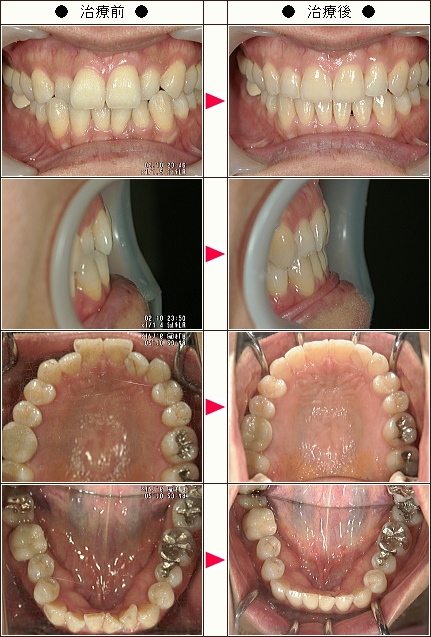

☆歯のデコボコ矯正症例[42歳 女性]